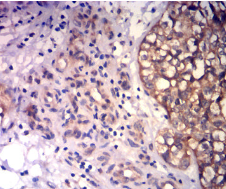

CD43 Mouse Monoclonal antibody[3E12F3]

IHC    1/200-1/1000